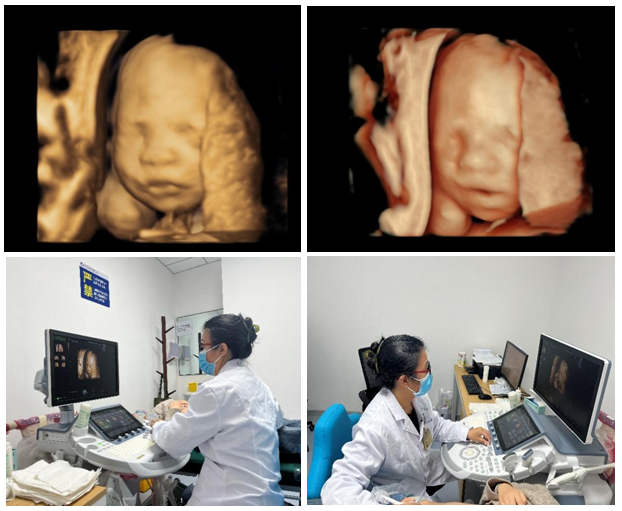

10月31日,超声诊断中心西咸院区为一位29岁的二胎孕妇,成功开展胎儿四维系统彩色多普勒超声检查,这是西咸院区的第一例胎儿四维系统超声检查。